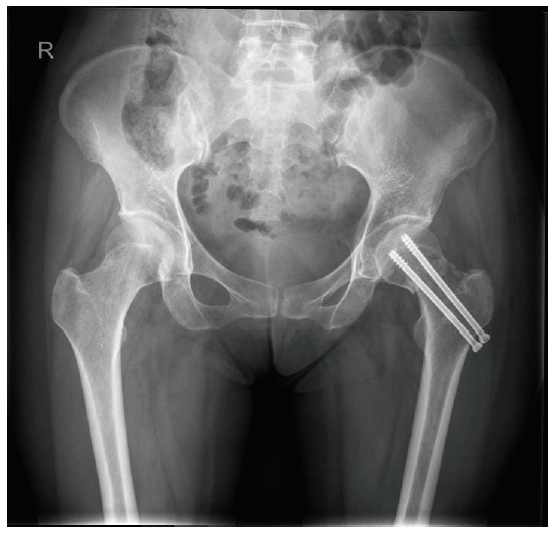

术中测得截取的髂骨大小为3.7 cm×0.8 cm,DCIA与髂前上棘的垂直距离为1.1 cm,远端血管距髂骨的垂直距离为1.0 cm,最后在距髂前上棘1.5 cm处与腹腔的血管相通,此处血管外径为0.6 mm,最终获得的带蒂髂骨瓣血管蒂长度为7.8 cm,见图2。术后3个月股骨X线片见图3,保髋治疗效果优良。

图3 左股骨颈骨折切开复位内固定结合DCIA带蒂髂骨瓣移植保髋术后3个月股骨X线片